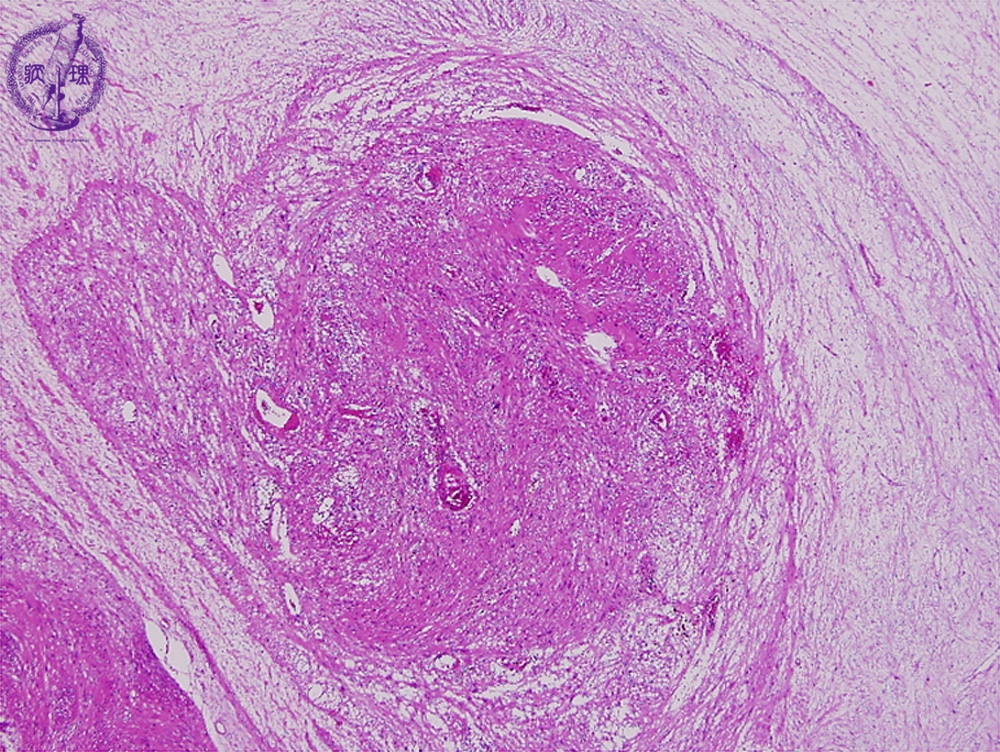

- ★(2)Schwannoma

Microscopic findings (H.E. low power view): Thecoexistence of cellular Antoni A area associated with proliferation of spindle cells and edematous Antoni B area associated with scattered spindle cells.